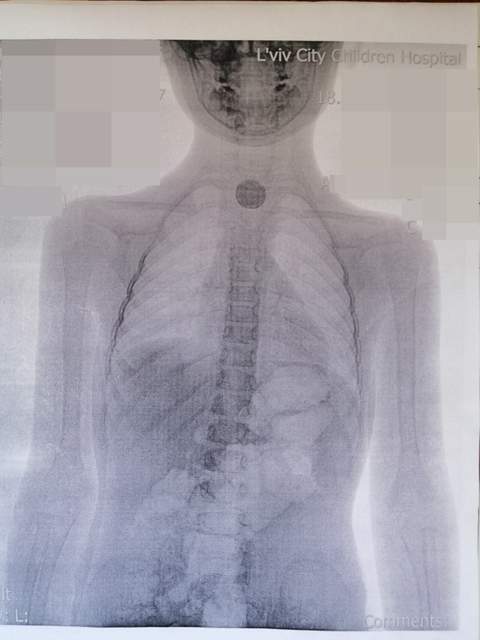

«У львівській міській дитячій лікарні дівчинці зробили рентген і скерували зі знімком до нас, в ОХМАТДИТ. На знімку видно було у стравоході стороннє тіло круглої форми. 11 липня ми прооперували дівчинку. Коли зайшли у стравохід, то зрозуміли, що вона проковтнула не монету, а батарейку: там було все чорне і обпечене», – каже Олександр Колодій.

Батарейка, що дістали зі стравоходу дитини, розміром з 25 копійок. Такі батарейки підходять до холодильників, а також деяких дитячих іграшок. У маленької дівчинки така батарейка спровокувала великий набряк і опік стравоходу.